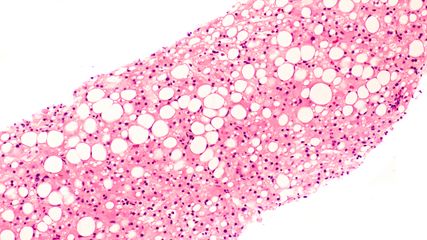

Fokale Leberläsionen sind nicht nur in der Gastroenterologie und Hepatologie, sondern auch in der internistischen und hausärztlichen Praxis ein häufiger Befund bei CT-, MRT- oder ...